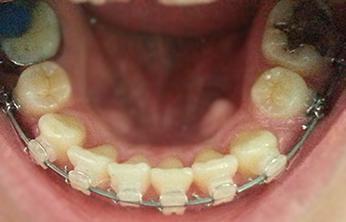

1년 반째 사진이에용 하악 좌측이 아직 덜 닫혀있네요.. @_@

발치공간이 다 닫히는데는 보통 1년~2년 정도 걸린다고 해요.

교정 초반에는 하악 발치공간이 찔끔찔끔 닫히는 것 같더니 어느 순간부터

이게 닫히긴 닫히는 건가~ 생각했던 것 같아요 ㅎ_ㅎ